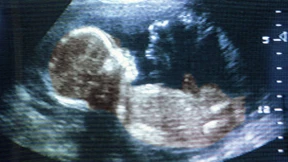

Den Bluttest, der feststellt, ob ein ungeborenes Kind Trisomie 21 hat, bezahlen wahrscheinlich bald die Kassen. Doch wie viel Wissen können werdende Eltern ertragen?

Pränataldiagnostik macht es möglich, sich vor der Geburt für oder gegen ein Kind mit Behinderung zu entscheiden. Doch wie reagieren werdende Eltern im Angesicht dieser Wahl?

Ein Junge oder ein Mädchen, und ist es gesund? Was wollen Schwangere vor der Geburt über das Ungeborene wissen? Grete Götze hat Ärzte, werdende und gewordene Eltern gefragt.

Wie neue Tests die Pränataldiagnostik und die Beratung herausfordern.